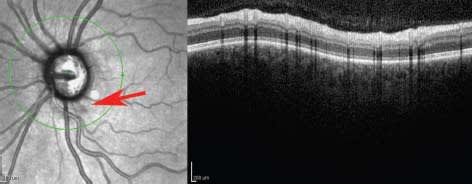

In patients with focal cataracts, OCT imaging can be directed around the opacity much more effectively than biomicroscopy (Figure 1). Other anterior segment opacities, such as corneal edema and corneal scars, may also prevent accurate fundus examination with ophthalmoscopy alone, but OCT can acquire adequate images even in these circumstances.

Figure 1. In this patient in whom a dense central lens opacity limited biomicroscopic observation, high-resolution OCT images demonstrated a normal macula by directing the OCT beam around the opacity.